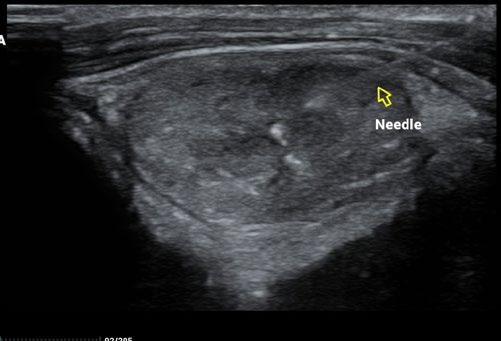

A cervical and thoracic CT scan (see figure 5 ) was performed to assess for evidence of local invasion or metastatic spread, and none was evident, so Taco was taken to surgery.

As a result, we ran full bloods, including a total T4, and confirmed hyperthyroidism. A fine needle aspirate of the nodule was consistent with a functional thyroid carcinoma.